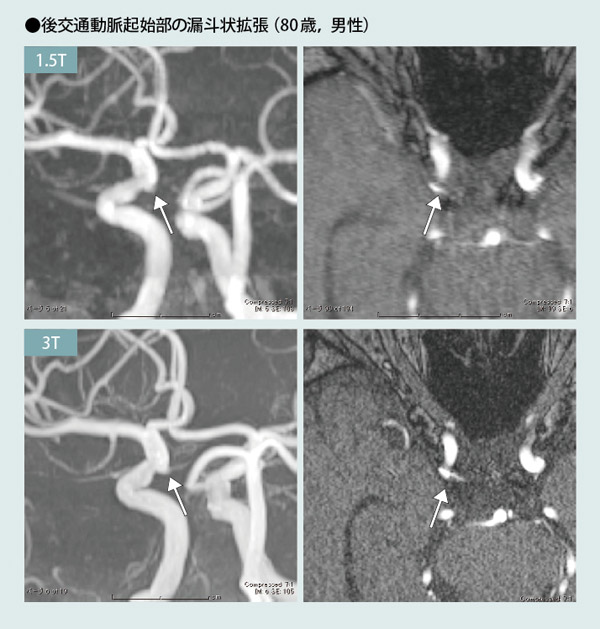

1.5T:1.5T装置でのMRA(左:MIP像,右:元画像)では,右内頸動脈に瘤状の像が見られ,動脈瘤が疑われる。後交通動脈自体は描出されていない。

3T:3T装置でのMRA(左:MIP像,左:元画像)では,上記の瘤状の像の先端から後交通動脈が連続しているのがわかる。動脈瘤ではなく,後交通動脈起始部の漏斗状拡張であることが判明した。